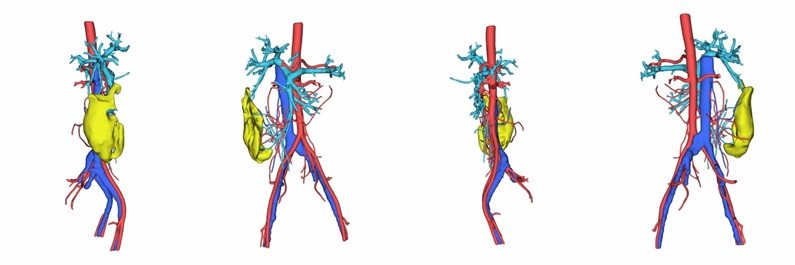

腹腔消化道的血液供应主要来自腹主动脉的分支,包括肠系膜上动脉和肠系膜下动脉。其静脉回流则较为特殊:血液由肠系膜上静脉和肠系膜下静脉等收集,汇合后形成门静脉。门静脉将血液输入肝脏进行代谢后,再经肝静脉汇入下腔静脉,最终返回心脏。

腹腔肿瘤包括肝肿瘤、脾肿瘤、肠系膜肿瘤等。三维重建技术在腹腔肿瘤的诊断、治疗和预后评估中具有重要作用。通过三维重建,可以更全面地展示肿瘤的位置、形态、侵犯范围以及与周围器官的关系,有助于医生制定更精确的手术方案和预后判断。此外,三维重建还可以用于评估手术效果和指导进一步的治疗,例如在机器人辅助手术中,三维重建技术可以提供更精确的手术导航和操作指导。

在胃癌手术前行双源CT增强扫描和腹腔血管三维重建,明确胃周血管的位置、解剖学特点及其变异情况,做好详细的手术预案,可明显缩短手术时间。、

↑胃肠病灶切除分析